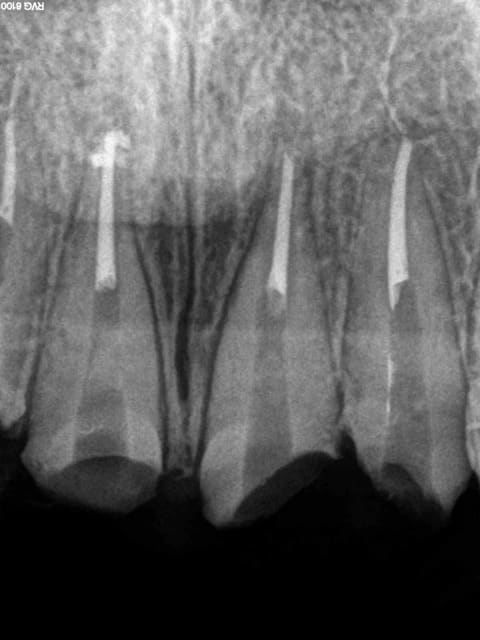

Ci dessous 7 radios, 1 det, une extrac : 118 euros 20 mn. Tu as quelque chose à redire ?

RDV d'une demi-heure initialement consult. légère gène sur 26 (tu m'étonnes). Radio de 26, anesthésie, status (antécédents de soins intensifs) detartrage, extraction. 5 mn pour le det, 2 mn pour l'extrac.

Le petit chicot au pays de la CCAM a encore frappé. -)))))